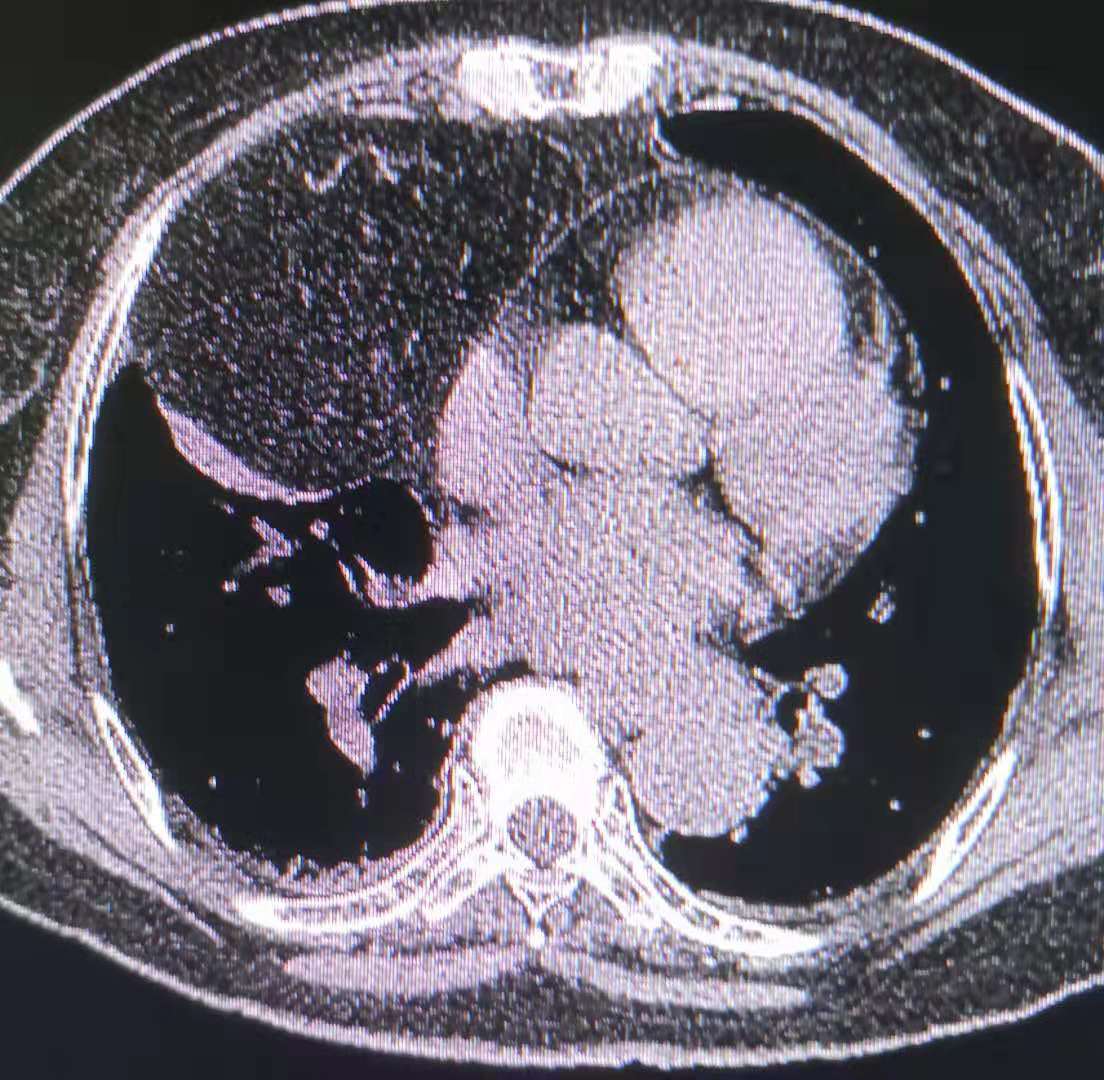

针对胸部的脂肪瘤,我院设备强大 的再重建功能显示,患者的膈肌上的巨大肿块影中有奇怪的积气现象。

往下追查,看到肿块来源于腹部,其中奇怪的气体影,是腹部的肠管。

最后的结论是腹部肠管及肠系膜疝入胸腔,患者长期的消化不良的现象得到了解释。